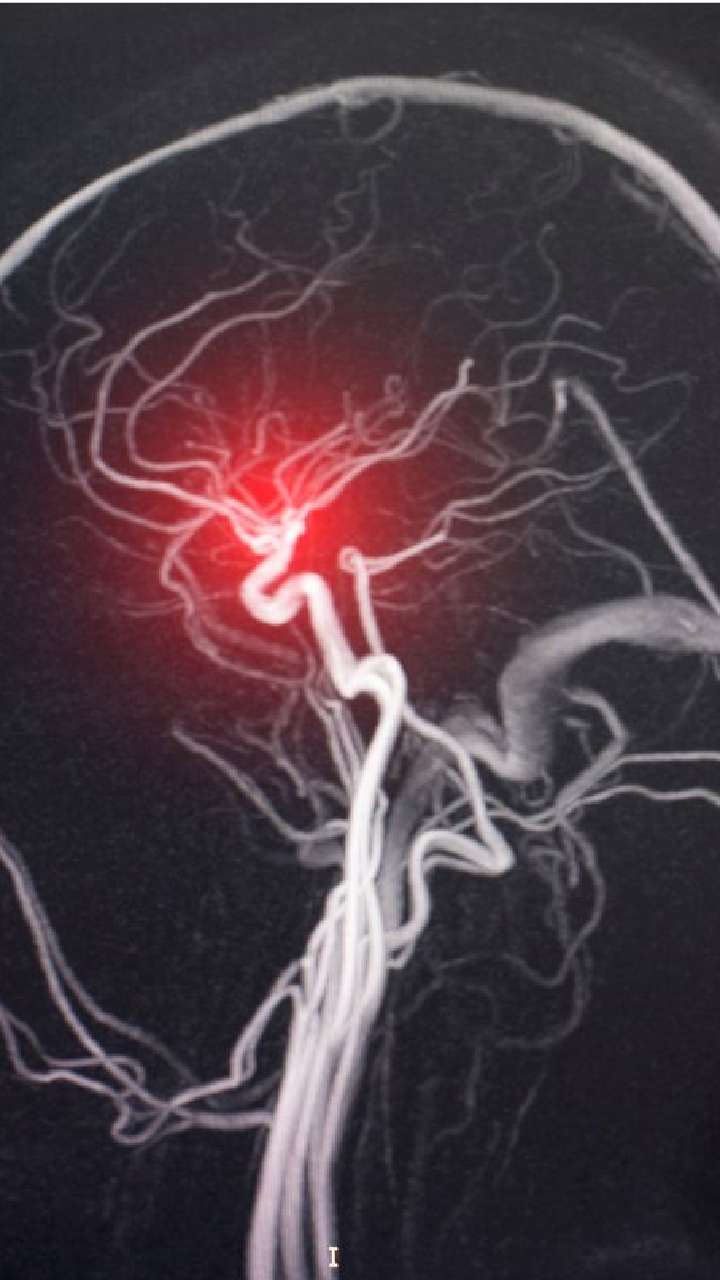

Neurosurgery

This field of medicine focuses on the diagnosis and treatment of patients with conditions that affect the brain, spinal cord and peripheral nerves.